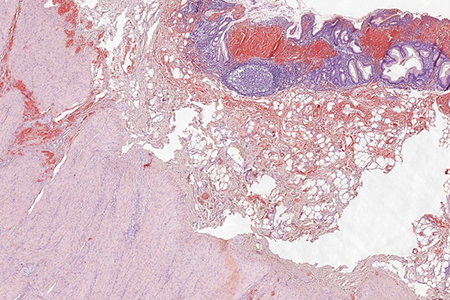

Histologically, lamina propria of gastric mucosa was expanded with amorphous paucicellular stromal deposits with cracking artifacts (Panels A and B). These depositions stained red with Congo Red stain (Panel C) and demonstrated characteristic apple-green birefringence in polarized light (Panel D). No malignancy was observed. Consequently, the final diagnosis was gastric amyloidosis.

Due to recurrent gastrointestinal bleeding and significant involvement of the stomach with amyloidosis, a distal resection of stomach was performed. Histological findings (Panel E) in the resection specimen, including Congo Red stain (Panel F) were similar to those described in the pre-operative biopsy.